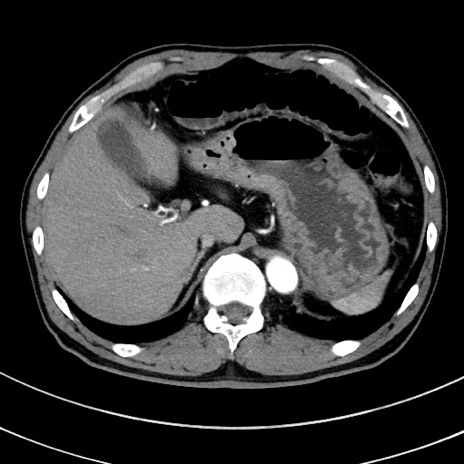

症例8(横断像)

【症例】 60歳代男性

【主訴】 黒色吐物

【現病歴】 4日前から嘔気自覚、2日前の朝食後にも嘔気あり、自分で手で嘔吐反射起こし嘔吐したところ血が混ざっていたため受診。

【既往歴】 5年前汎発性腹膜炎を伴う急性虫垂炎で手術、高血圧、前立腺肥大症、高脂血症

【身体所見】 腹部正中に手術癩痕あり 腹部平坦・軟圧痛なし膨満感あり

【データ】WBC 8400、CRP 4.54